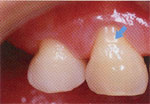

矢印のところが知覚過敏を起こしている部分。ふつうは見てもわからない。 水や空気をかけると痛い。おいしく食事ができなかったり、日常生活が不快です。